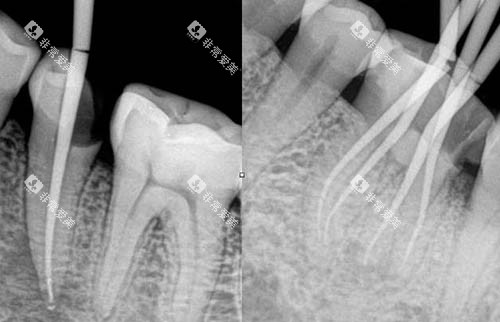

较高的医疗设备

该门诊部引进了一系列国内外较高的口腔医疗设备,如智能化口腔全景机、口腔 CT、激光治疗设备等。

这些设备能够为医生提供较准的诊断依据,提高治疗的比较准度和靠谱性。

以智能化口腔全景机为例,它可以快速、清晰地拍摄口腔全景图像,让医生齐全了解患者的口腔状况,为制定治疗方案提供有力支持。

同时,较高的设备也能减少患者的治疗时间和痛苦,提高治疗结果。